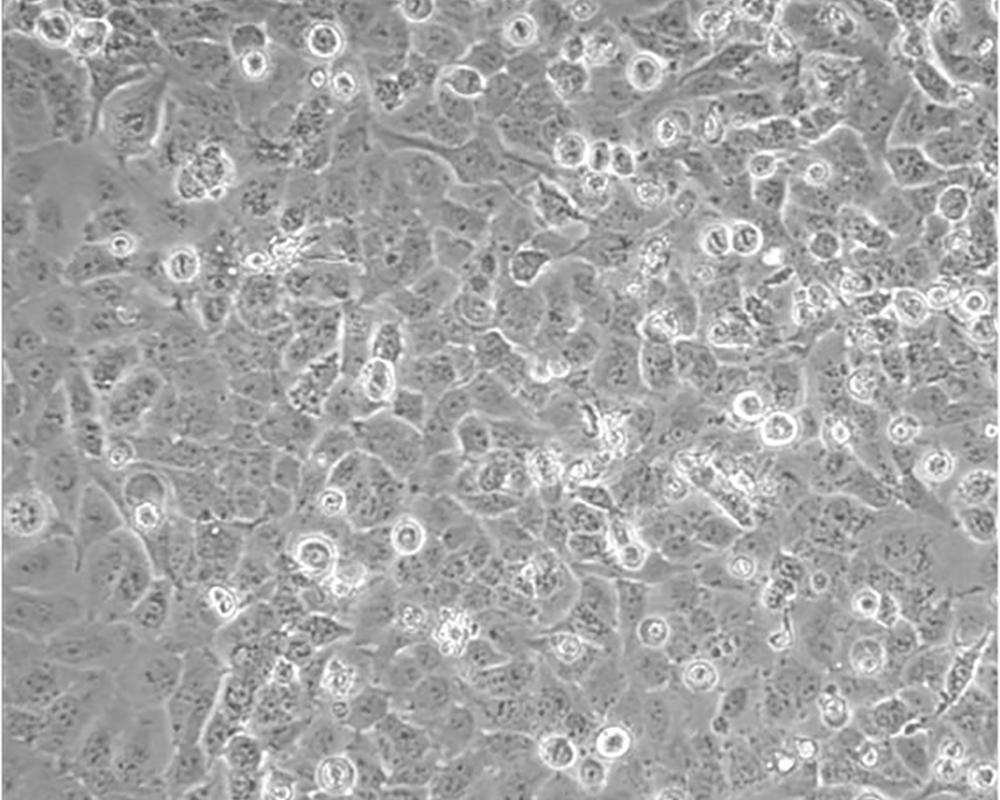

NCI-H23

組織來源 肺腺癌;男性

細胞種屬 Homo sapiens, human

形態(tài)特征 epithelial

細胞描述 該細胞源于一位51歲患有非小細胞肺癌黑人男性患者的治療前的腫瘤組織,表達C-myc、L-myc、v-src、v-abl、v-erb B、c-raf 1、Ha-ras、Ki-ras、N-ras RNAs;該細胞攜帶K-ras 12突變;p53基因246位密碼子突變ATC→ATG;表達PDGF A和B鏈的異源mRNA;表達TGFα、TGFβ和EGFR;角蛋白 5、8和18陽性,波形蛋白陽性,神經(jīng)絲蛋白陰性,左旋多巴脫氫酶陰性;據(jù)報道,在軟瓊脂中該細胞形成克隆的效率為9.7%。